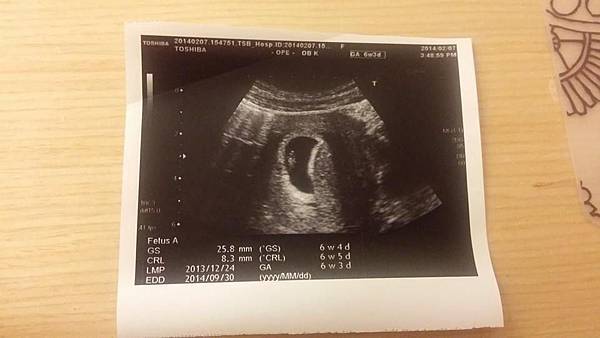

從一個小豆子~

到下次產檢看到了我的小寶貝!!!

超級小的小番薯哈哈哈~

真的很像嘛((扭~

然後慢慢變成了一個小人型~

好可愛喔!!!